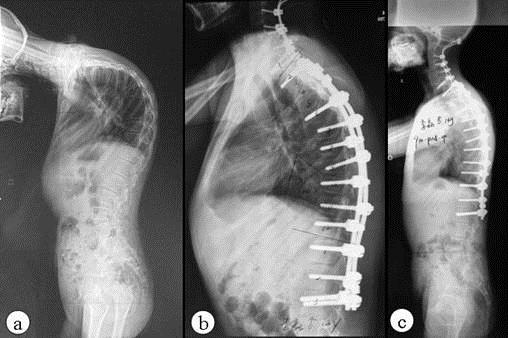

AS ①晚期 ②重度 病史:5年+

- 治疗

治疗后骶髂关节疼痛消失,腰椎前屈、背伸侧弯活动自如,膝关节无压痛感,复查血沉、C反应蛋白、等各项检查均已达到临床康复的标准。